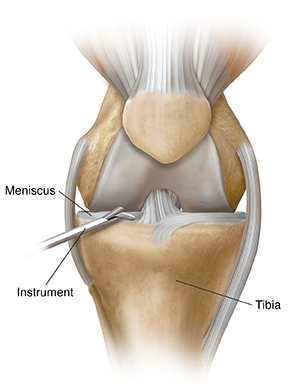

Meniscal cartilage tears

There are several types of meniscal cartilage tears. The meniscal cartilage is attached to the tibia (shinbone). It acts as a shock absorber for the knee. Your surgery will depend on the type and extent of your injury. Your surgeon can remove the damaged tissue or fix the tear. Treatment should ease the pain and swelling. It can also help keep the joint from locking.

| Damaged meniscal cartilage is removed. |